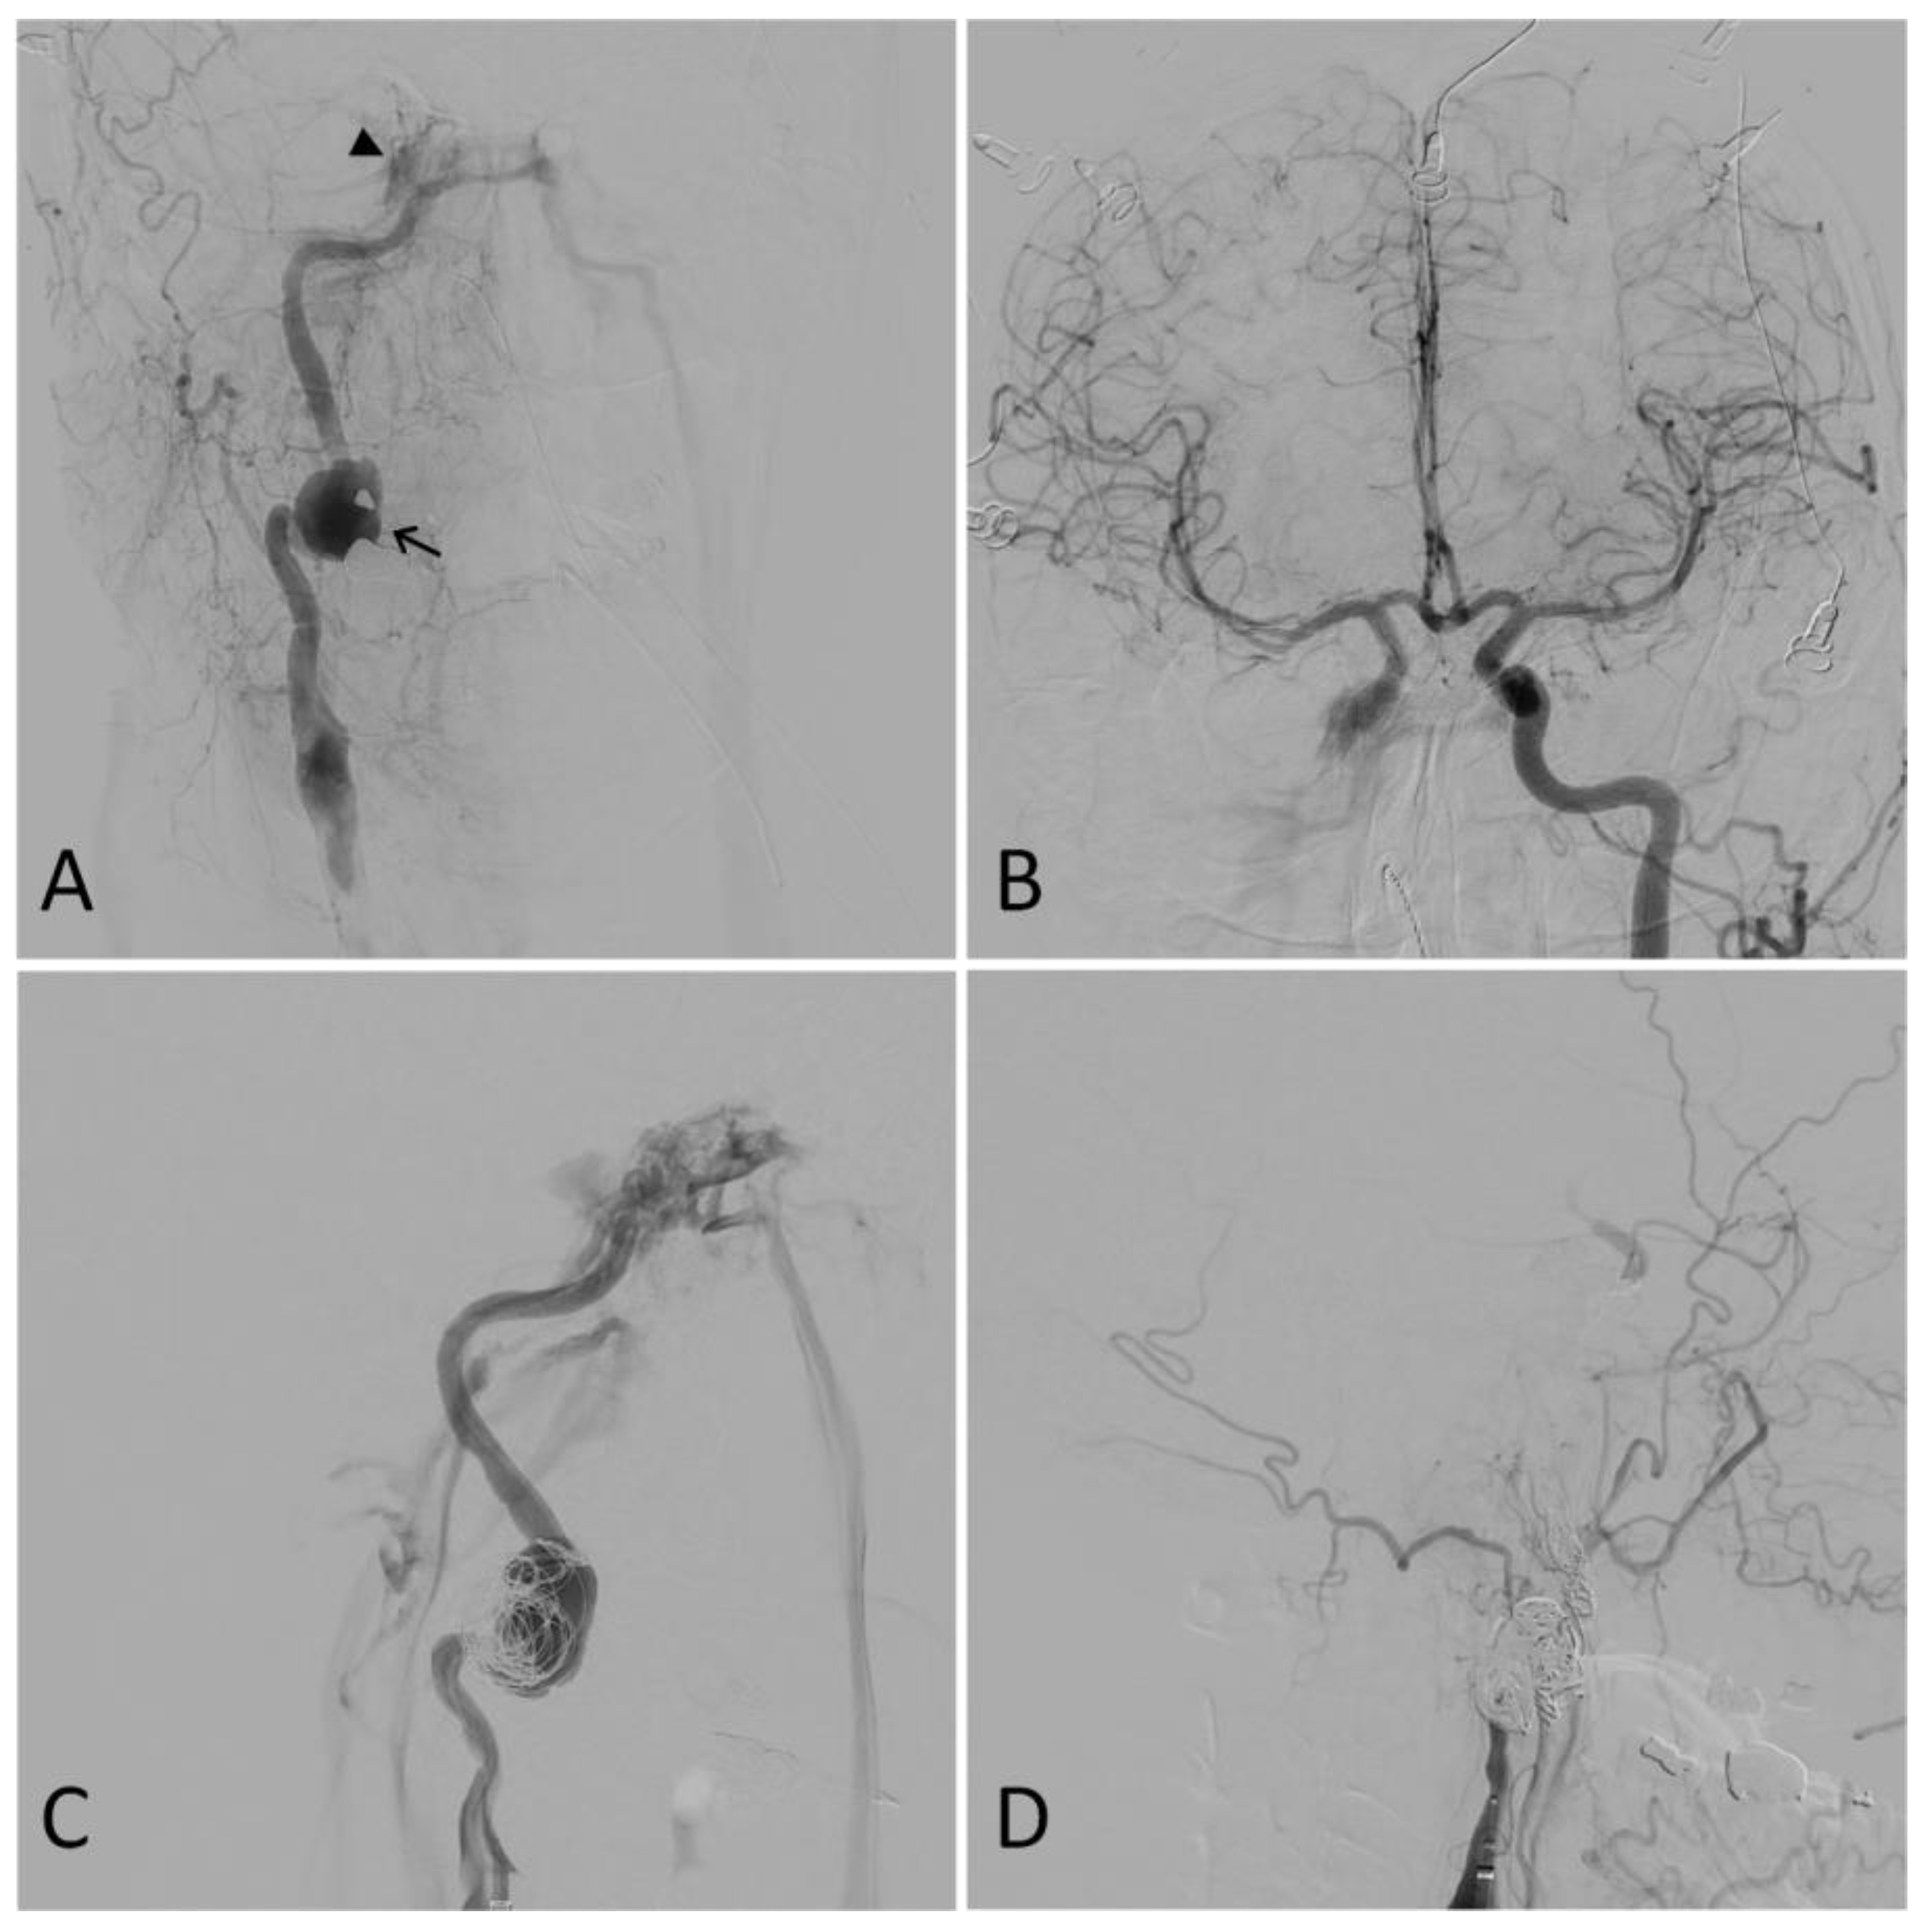

Carotid-cavernous fistula (CCF), a type of arteriovenous malformation, is typically associated with complex fractures of the skull base and can form as a result of cranial trauma (Figure 3). Following injury, arterialization of the venous outflow from the cavernous sinus may result in the development of a myriad of symptoms, including visual deterioration, ophthalmoplegia, diplopia, headache, conjunctival chemosis, proptosis, pulsatile tinnitus, and ocular bruit [5,54,55,56,57]. These signs and symptoms may develop days to weeks following the initial traumatic event [5]. Initial evaluation of a CCF patient includes standard ocular tonometry, pneumotonometry, ultrasonography, color Doppler imaging, CTA, and/or MRA [56].

Illustrative case. A 50-year-old male presented after a motor vehicle accident. A computed tomography angiogram revealed a right internal carotid artery (ICA) pseudoaneurysm with associated stenosis. A digital subtraction angiogram showed a 27 mm right ICA dissecting pseudoaneurysm (arrow) and a right carotid-cavernous fistula (CCF) (arrowhead) (A). Furthermore, the right anterior circulation was noted to fill completely through the left ICA (B). Partial coil embolization was performed at this time to protect the dome of the pseudoaneurysm (C). A repeat angiogram two weeks later showed the right ICA was dissected throughout its entire course and ended in a false lumen in the supraclinoid segment with no antegrade flow or intracranial filling. The CCF, pseudoaneurysm, and dissected ICA were then coiled. A final right common carotid angiogram showed no filling of the ICA, pseudoaneurysm, or CCF (D).